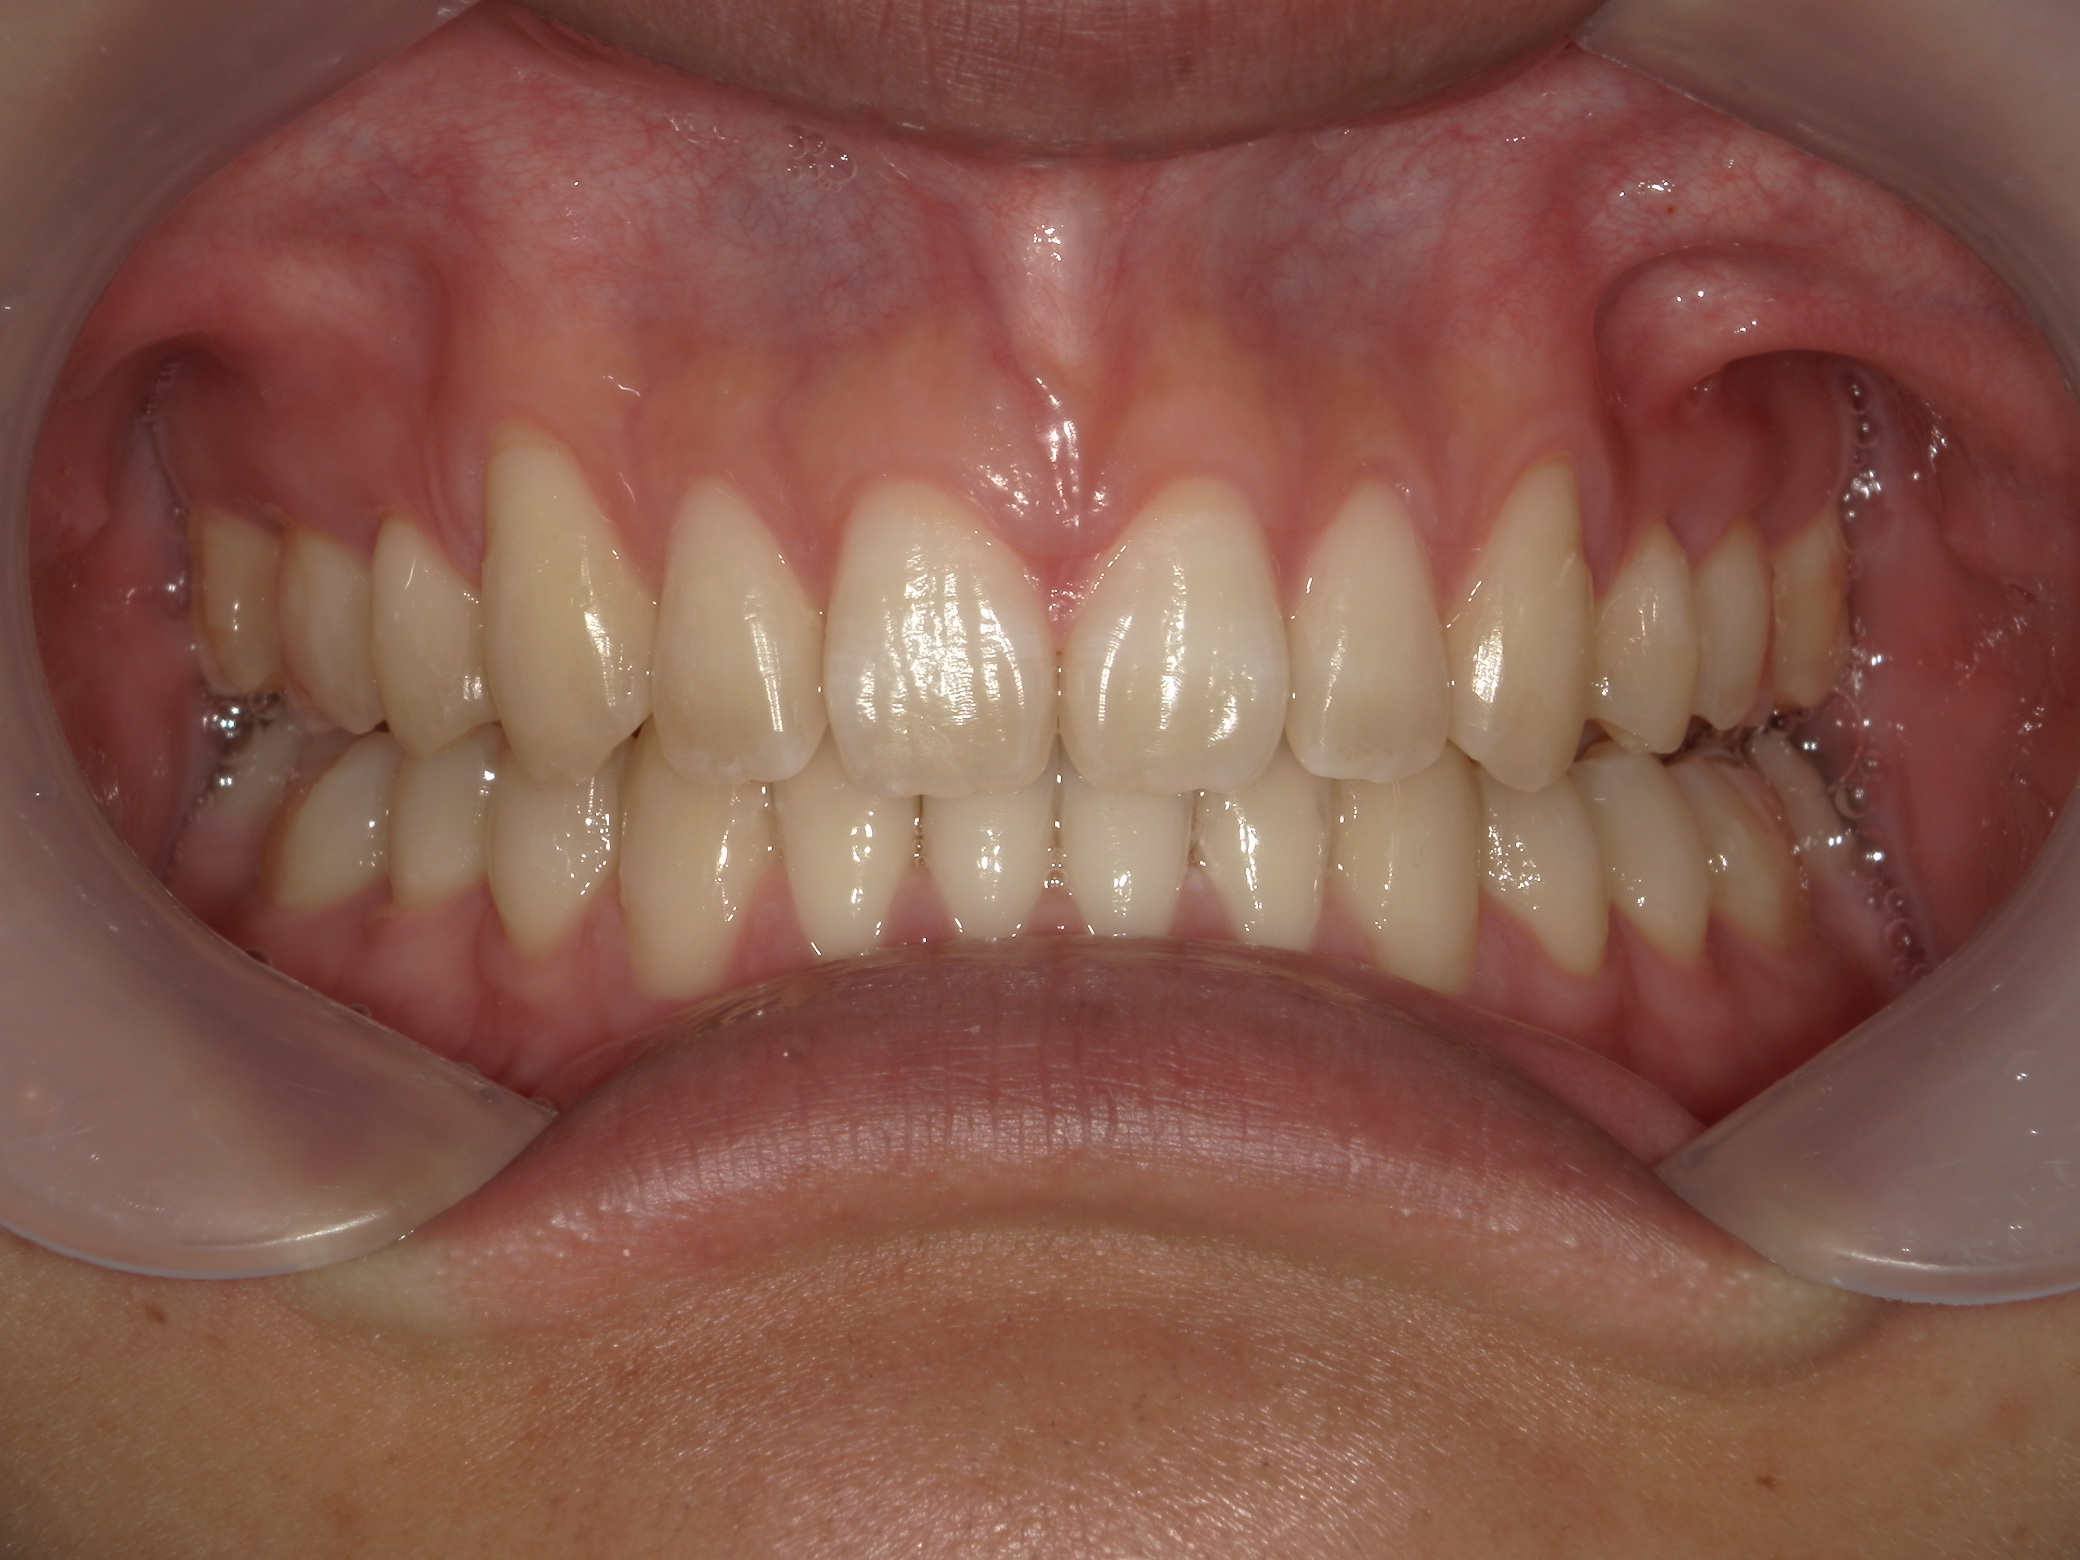

インビザライン矯正 症例(24)

主訴: 前歯の隙間が気になる。

左右上 第一小臼歯(2本)を抜歯。

スライスカットを併用。

カテゴリー : 隙間がある(空隙歯列)